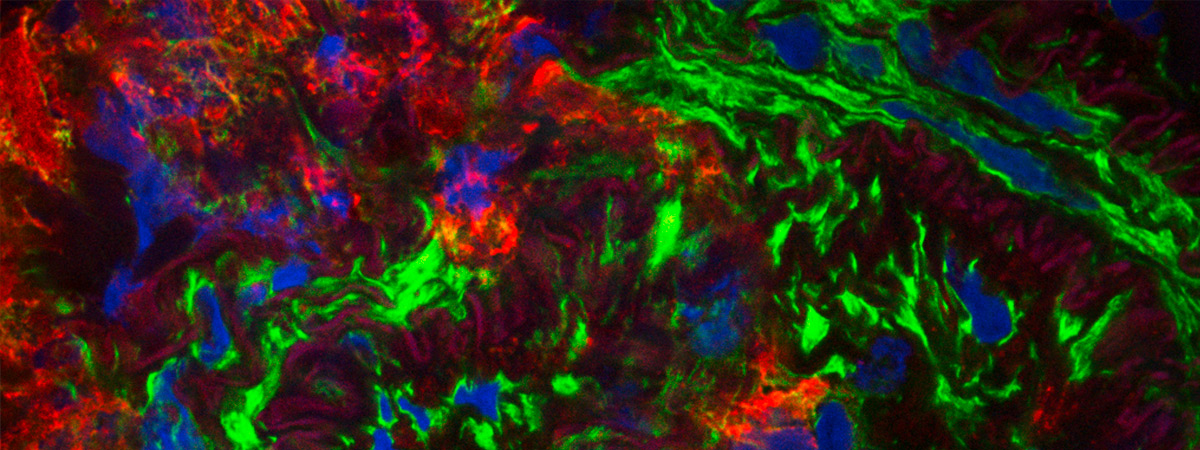

Idiopathic and heritable forms of pulmonary arterial hypertension (PAH) are devastating conditions associated with high morbidity and mortality. The disease is usually diagnosed late by finding a markedly increased pulmonary arterial pressure (increased blood pressure in the arteries of the lungs), the result of progressive narrowing and obliteration of the pulmonary vasculature, which often results in failure of the right ventricle. This disease tends to present in the middle decades of life, with a female predominance.

A major breakthrough in our understanding of the molecular basis of hypertension PAH was the identification of heterozygous germline mutations in the bone morphogenetic protein type II receptor (BMPR-II) in the majority (>70%) of familial cases of the disease and a significant proportion (15-26%) of sporadic cases. Although the presence of mutations in BMPR-II is the greatest risk factor for the development of PAH, it is estimated that only 20% of carriers develop the disease. Additional factors are required for disease manifestation. These may be genetic and/or environmental, though the identity of these factors remains unknown.